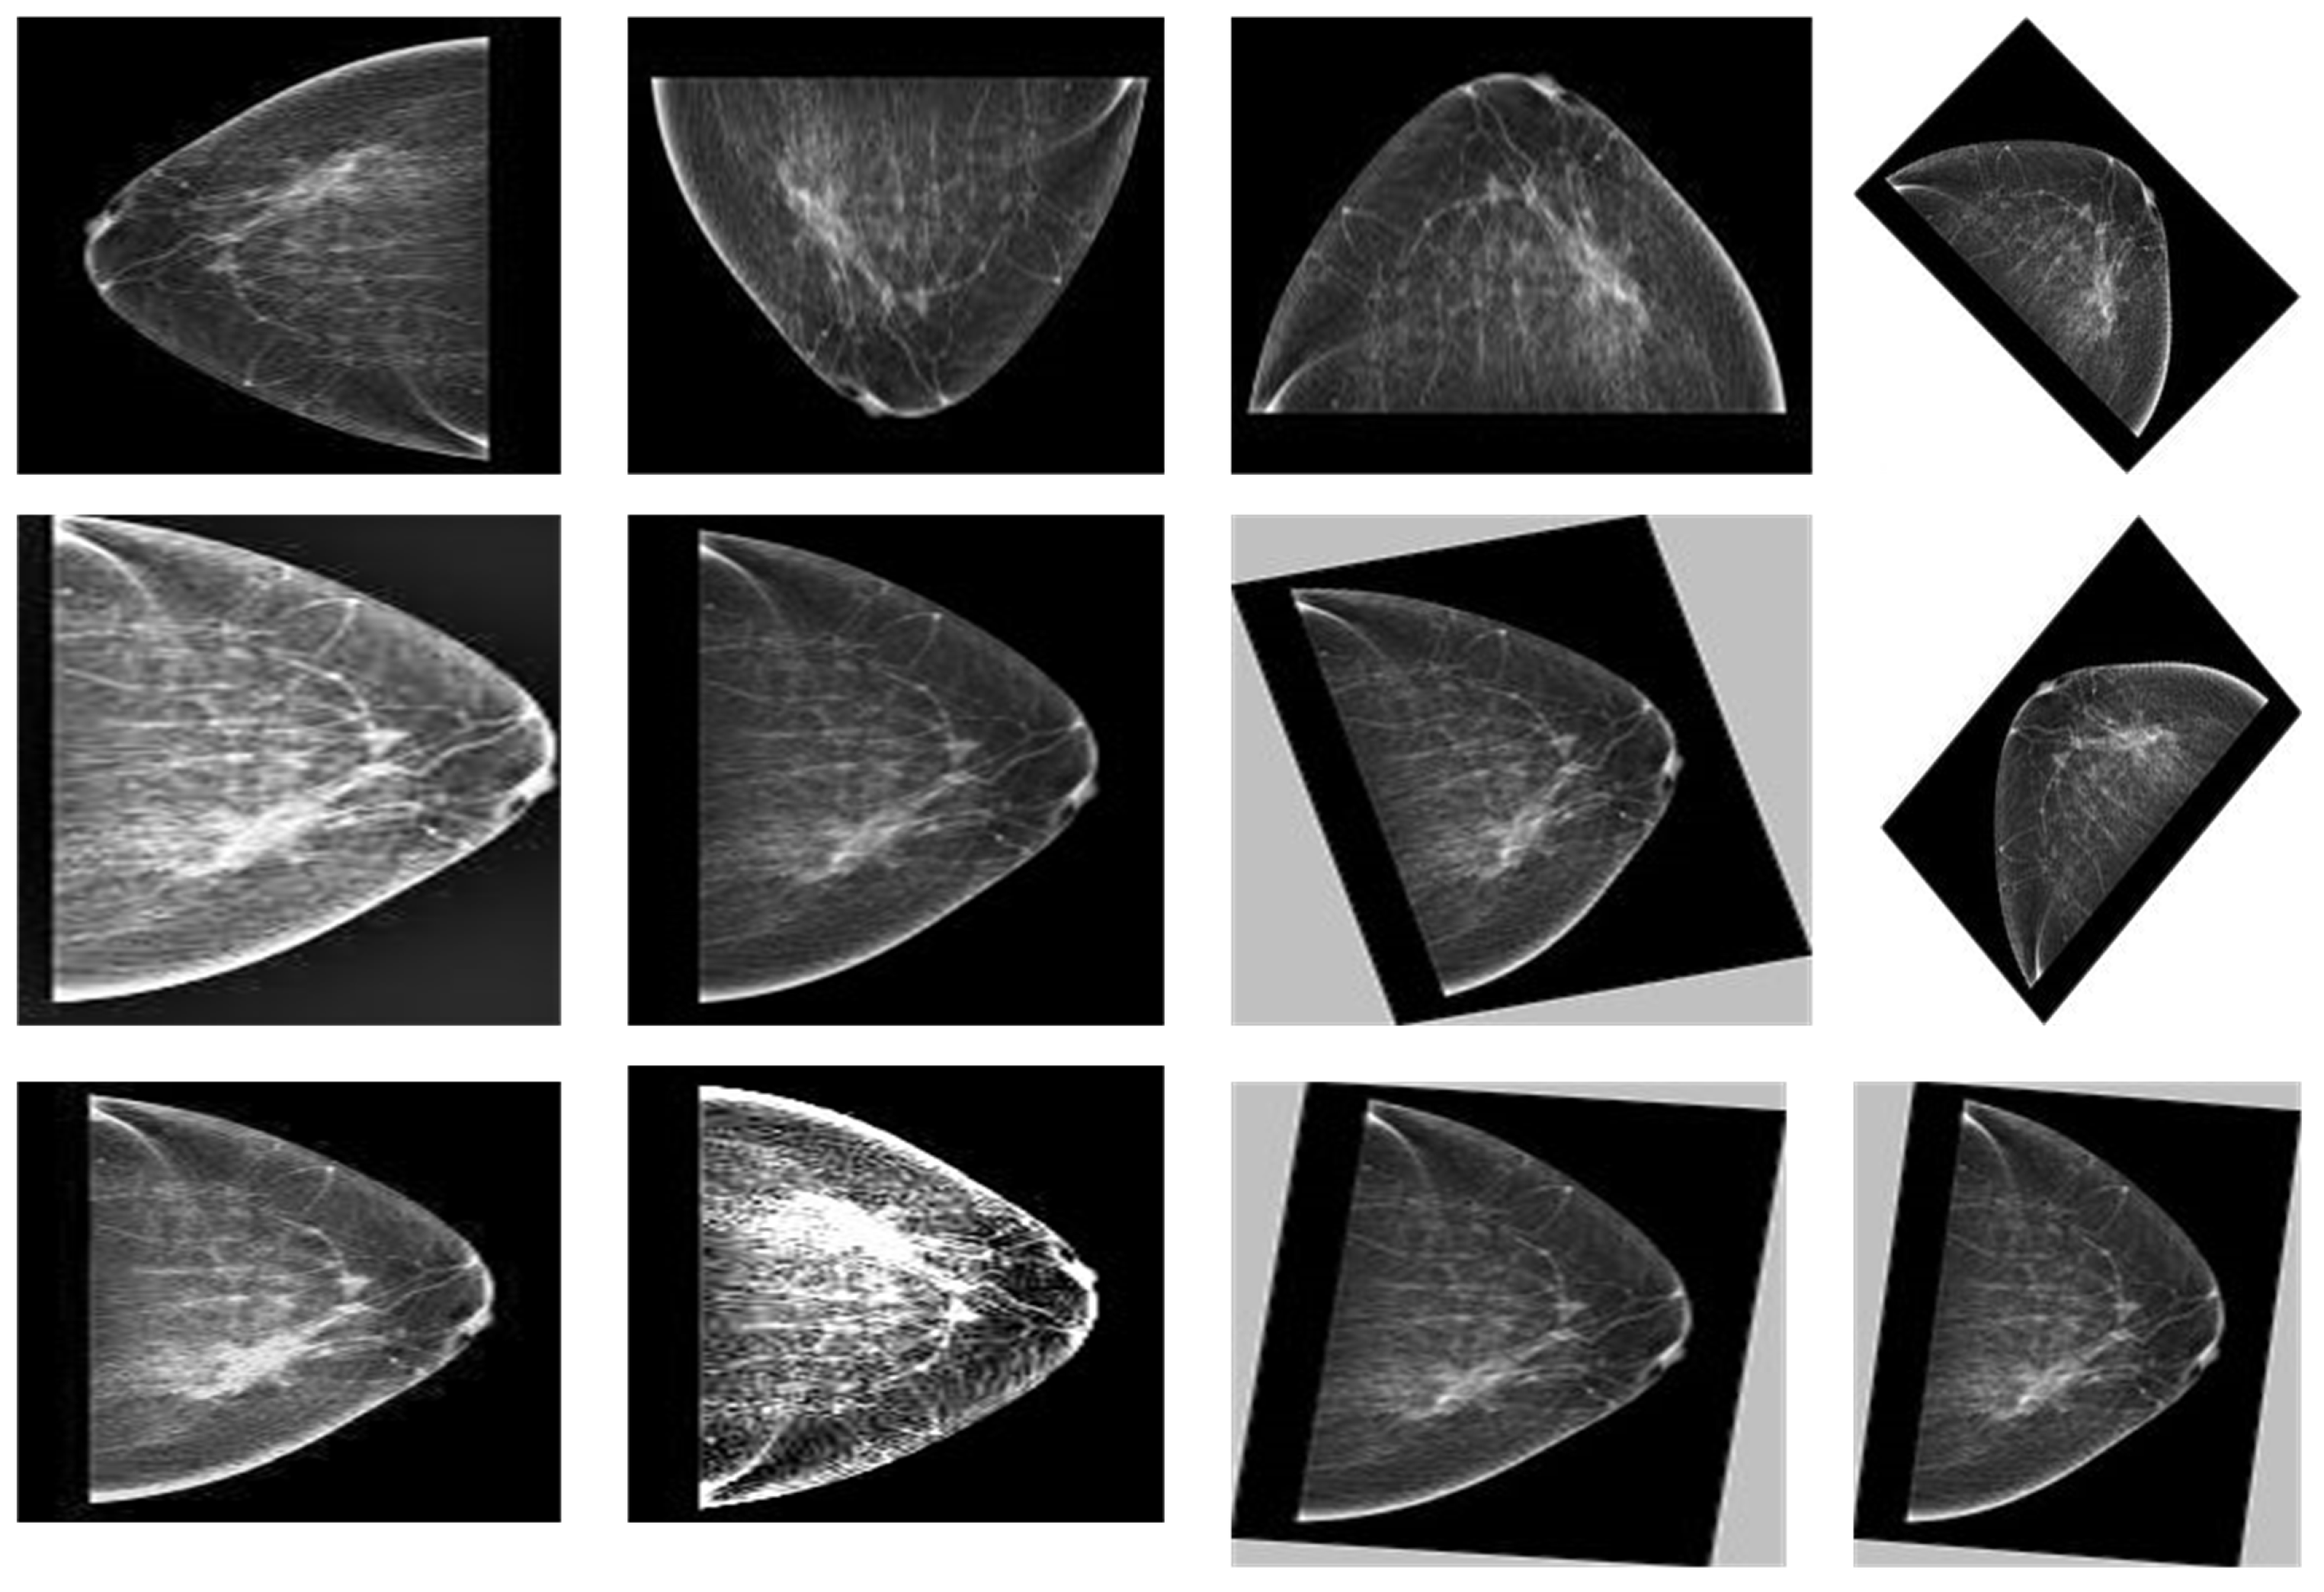

4.3. Image Augmentation

| Sr | Augmentation Techniques | Performance Values |

| 1 | Rotation | 45, 90, 135, 180, 360 |

| 2 | Flipping | Left, Right, Top, Bottom |

| 3 | Sharpen (lightness value) | 0.5–1.5 |

| 4 | D-skew (angle) | 15, 40 |

| 5 | Contrast (intensity value) | 20–60% |

| 6 | Brightness (darkness values) | 15–55% |